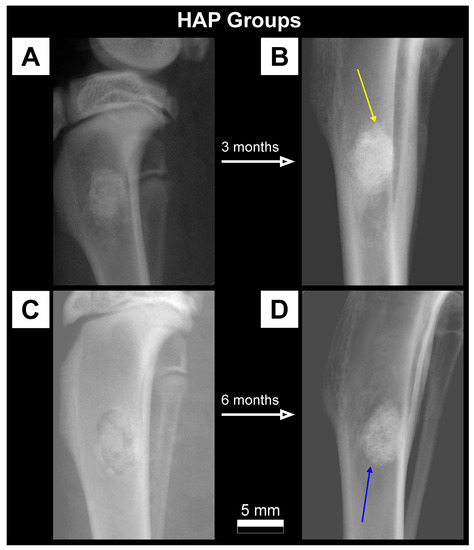

2.3.1. X-ray Imaging—Conventional Radiography

3.1. Qualitative Analysis of Bone Substitute Materials